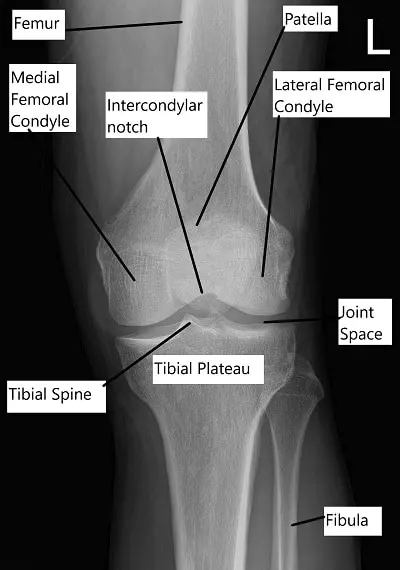

X-ray showing knee anatomy.

The knee is formed by four bones:

Femur (thighbone), tibia (shinbone), patella (kneecap), and fibula (a thin bone alongside the tibia).

The upper ends of the tibia and femur create the main knee joint, while the patella sits in front and glides as the knee bends. The joint is lined by synovium, which makes fluid that nourishes the joint.